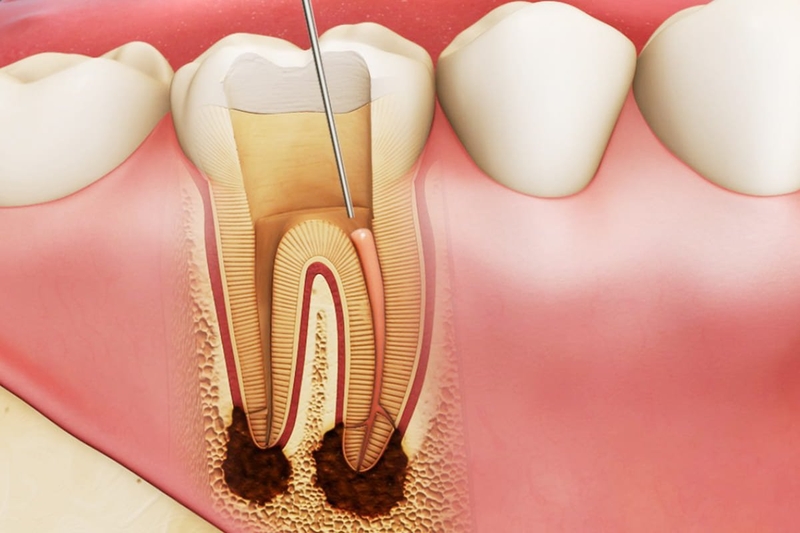

Sâu chân răng không chỉ gây khó chịu và đau nhức mà còn có thể dẫn đến nhiều hậu quả nghiêm trọng nếu không được điều trị kịp thời. Nhiều người thường xem nhẹ dấu hiệu sâu chân răng, dẫn đến các biến chứng nguy hiểm, thậm chí mất răng vĩnh viễn. Vậy sâu chân răng có thể gây ra những hậu quả gì? Sau đây là một số tác hại của sâu chân răng gây nên:

Sâu chân răng là một vấn đề răng miệng phổ biến nhưng có thể gây ra nhiều hậu quả nghiêm trọng nếu không được phát hiện và điều trị kịp thời. Việc hiểu rõ nguyên nhân gây bệnh giúp mỗi người có thể chủ động phòng tránh, từ đó bảo vệ răng miệng một cách hiệu quả. Bằng cách duy trì thói quen vệ sinh răng miệng đúng cách, kiểm soát chế độ ăn uống và thăm khám nha khoa định kỳ, chúng ta có thể ngăn ngừa sâu chân răng và giữ cho hàm răng luôn chắc khỏe.